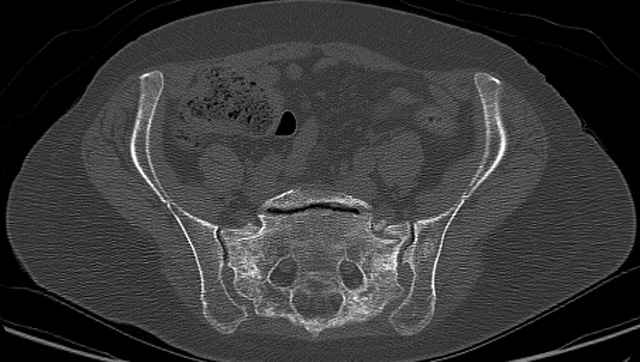

3 Months After Fall

Continued Pain & Immobility

(+) Instability to Compressive Manual Exam

Pelvic CT Scan - 3 Months After Fall

Sacral Injuries

Ramus Fractures